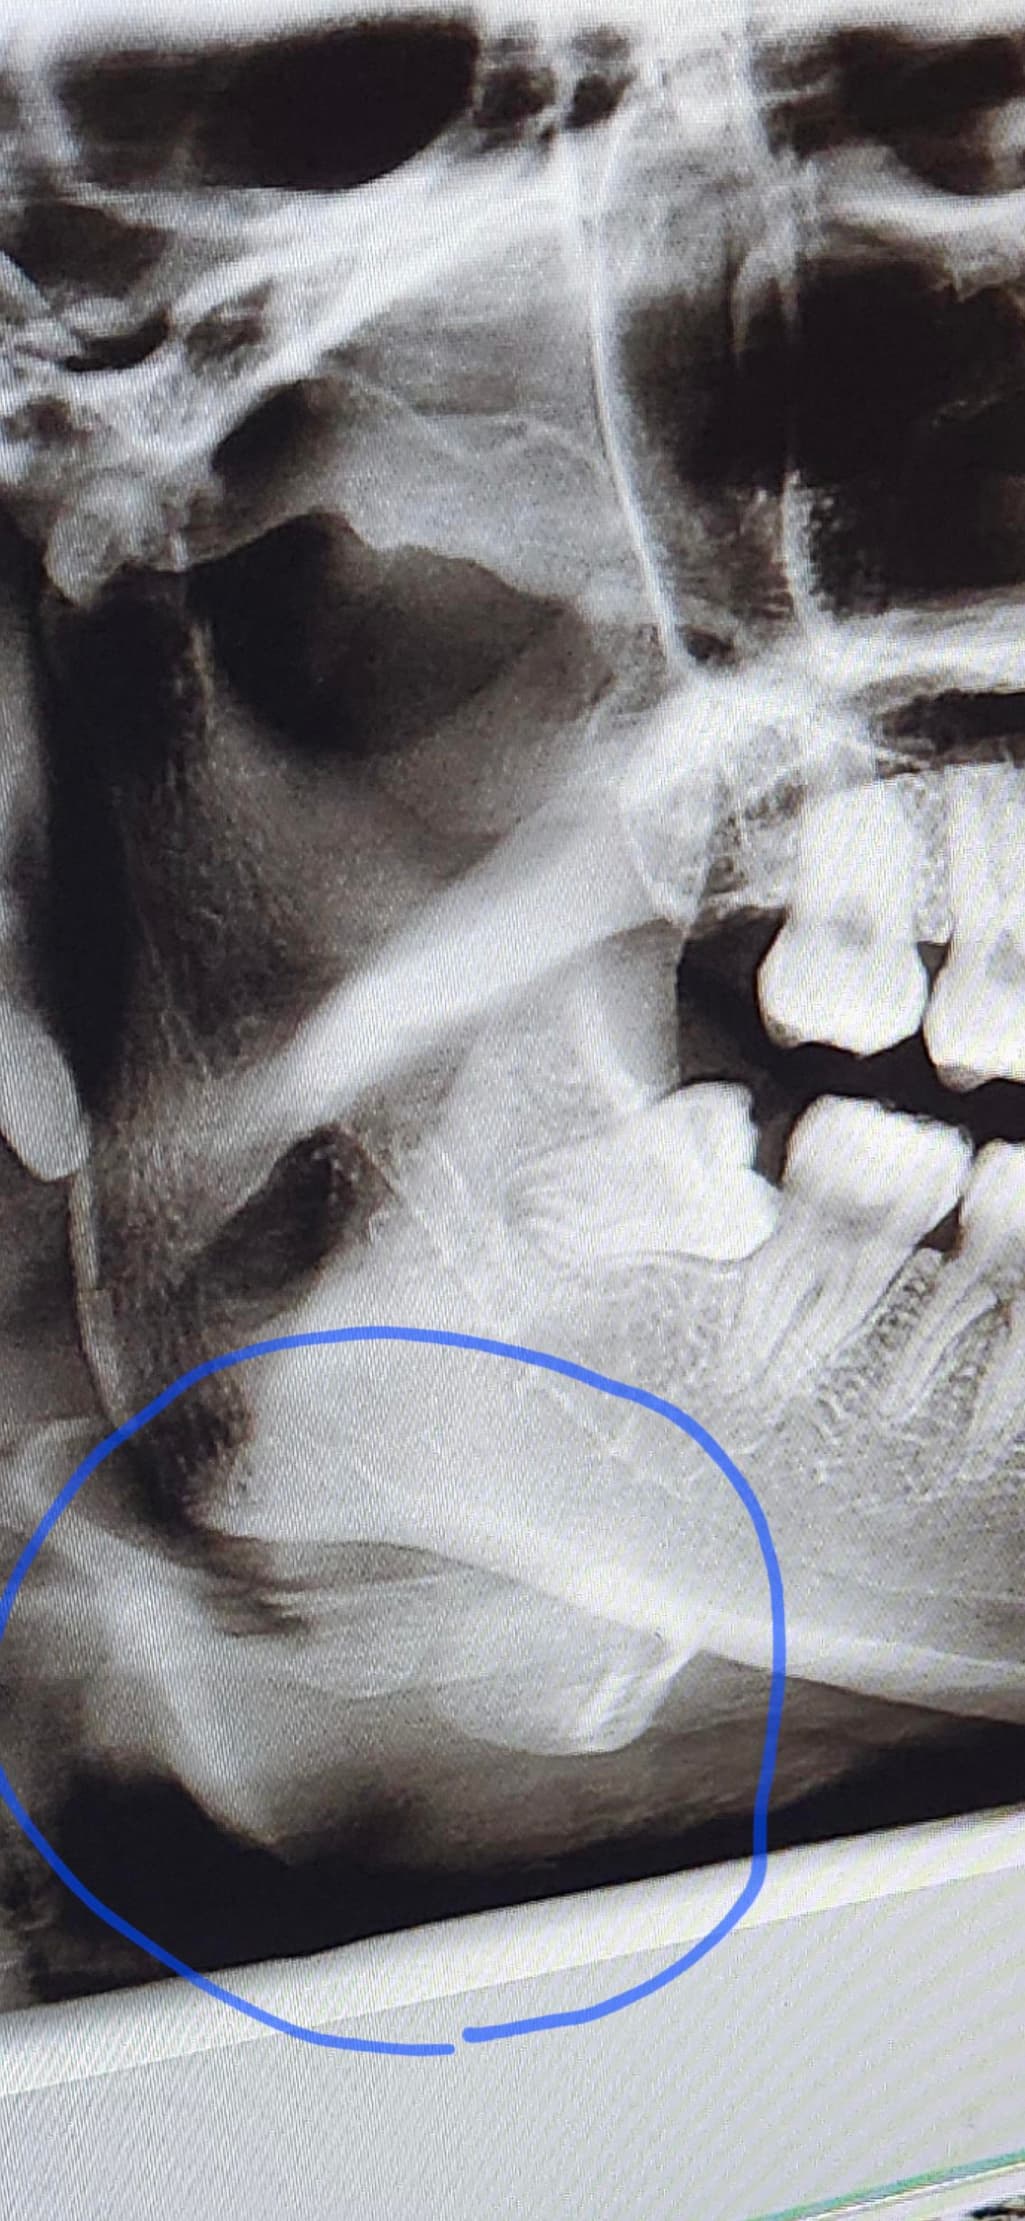

치과 엑스레이 턱에 하얀 부분 뭔가요?

동그라미 친 부분이 뭔지 궁금합니다

설마 치아는 아니겠죠? 왜 저렇게 치아같은 모양으로 있는건지 좀 알려주세요..

동그라미 친 부분은 치아 모양이 아니며 설골일 가능성이 높습니다.

이상있는 것 아닙니다. 치과 파노라마 사진은 회전하면서 찍어서 회전할 때 그림자가 생겨서 색깔이 다르게 보이는 것입니다. 무시하면 됩니다.

정상 해부학적 구조(뼈)입니다 hyoid bone panoramic x ray라고 검색해보시기 바랍니다

사진으로 보이는 부분은 설골이 있는 부분으로 보입니다. 앞 꼴에 있는 것이 아니라 목에 있는 뼈가 방사선 사진상으로 보인 것으로 보입니다.